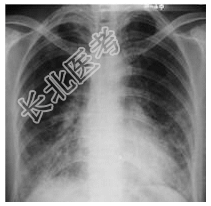

- [材料题] 患者,男性,55岁。咳嗽、发热1周入院。查体:体温,38.1℃;双肺呼吸音粗,双下肺可闻及细湿啰音。心脏听诊无异常。行胸部正位片检查。

- 简答题1、诊断及依据是什么?

- 简答题2、鉴别诊断有哪些?